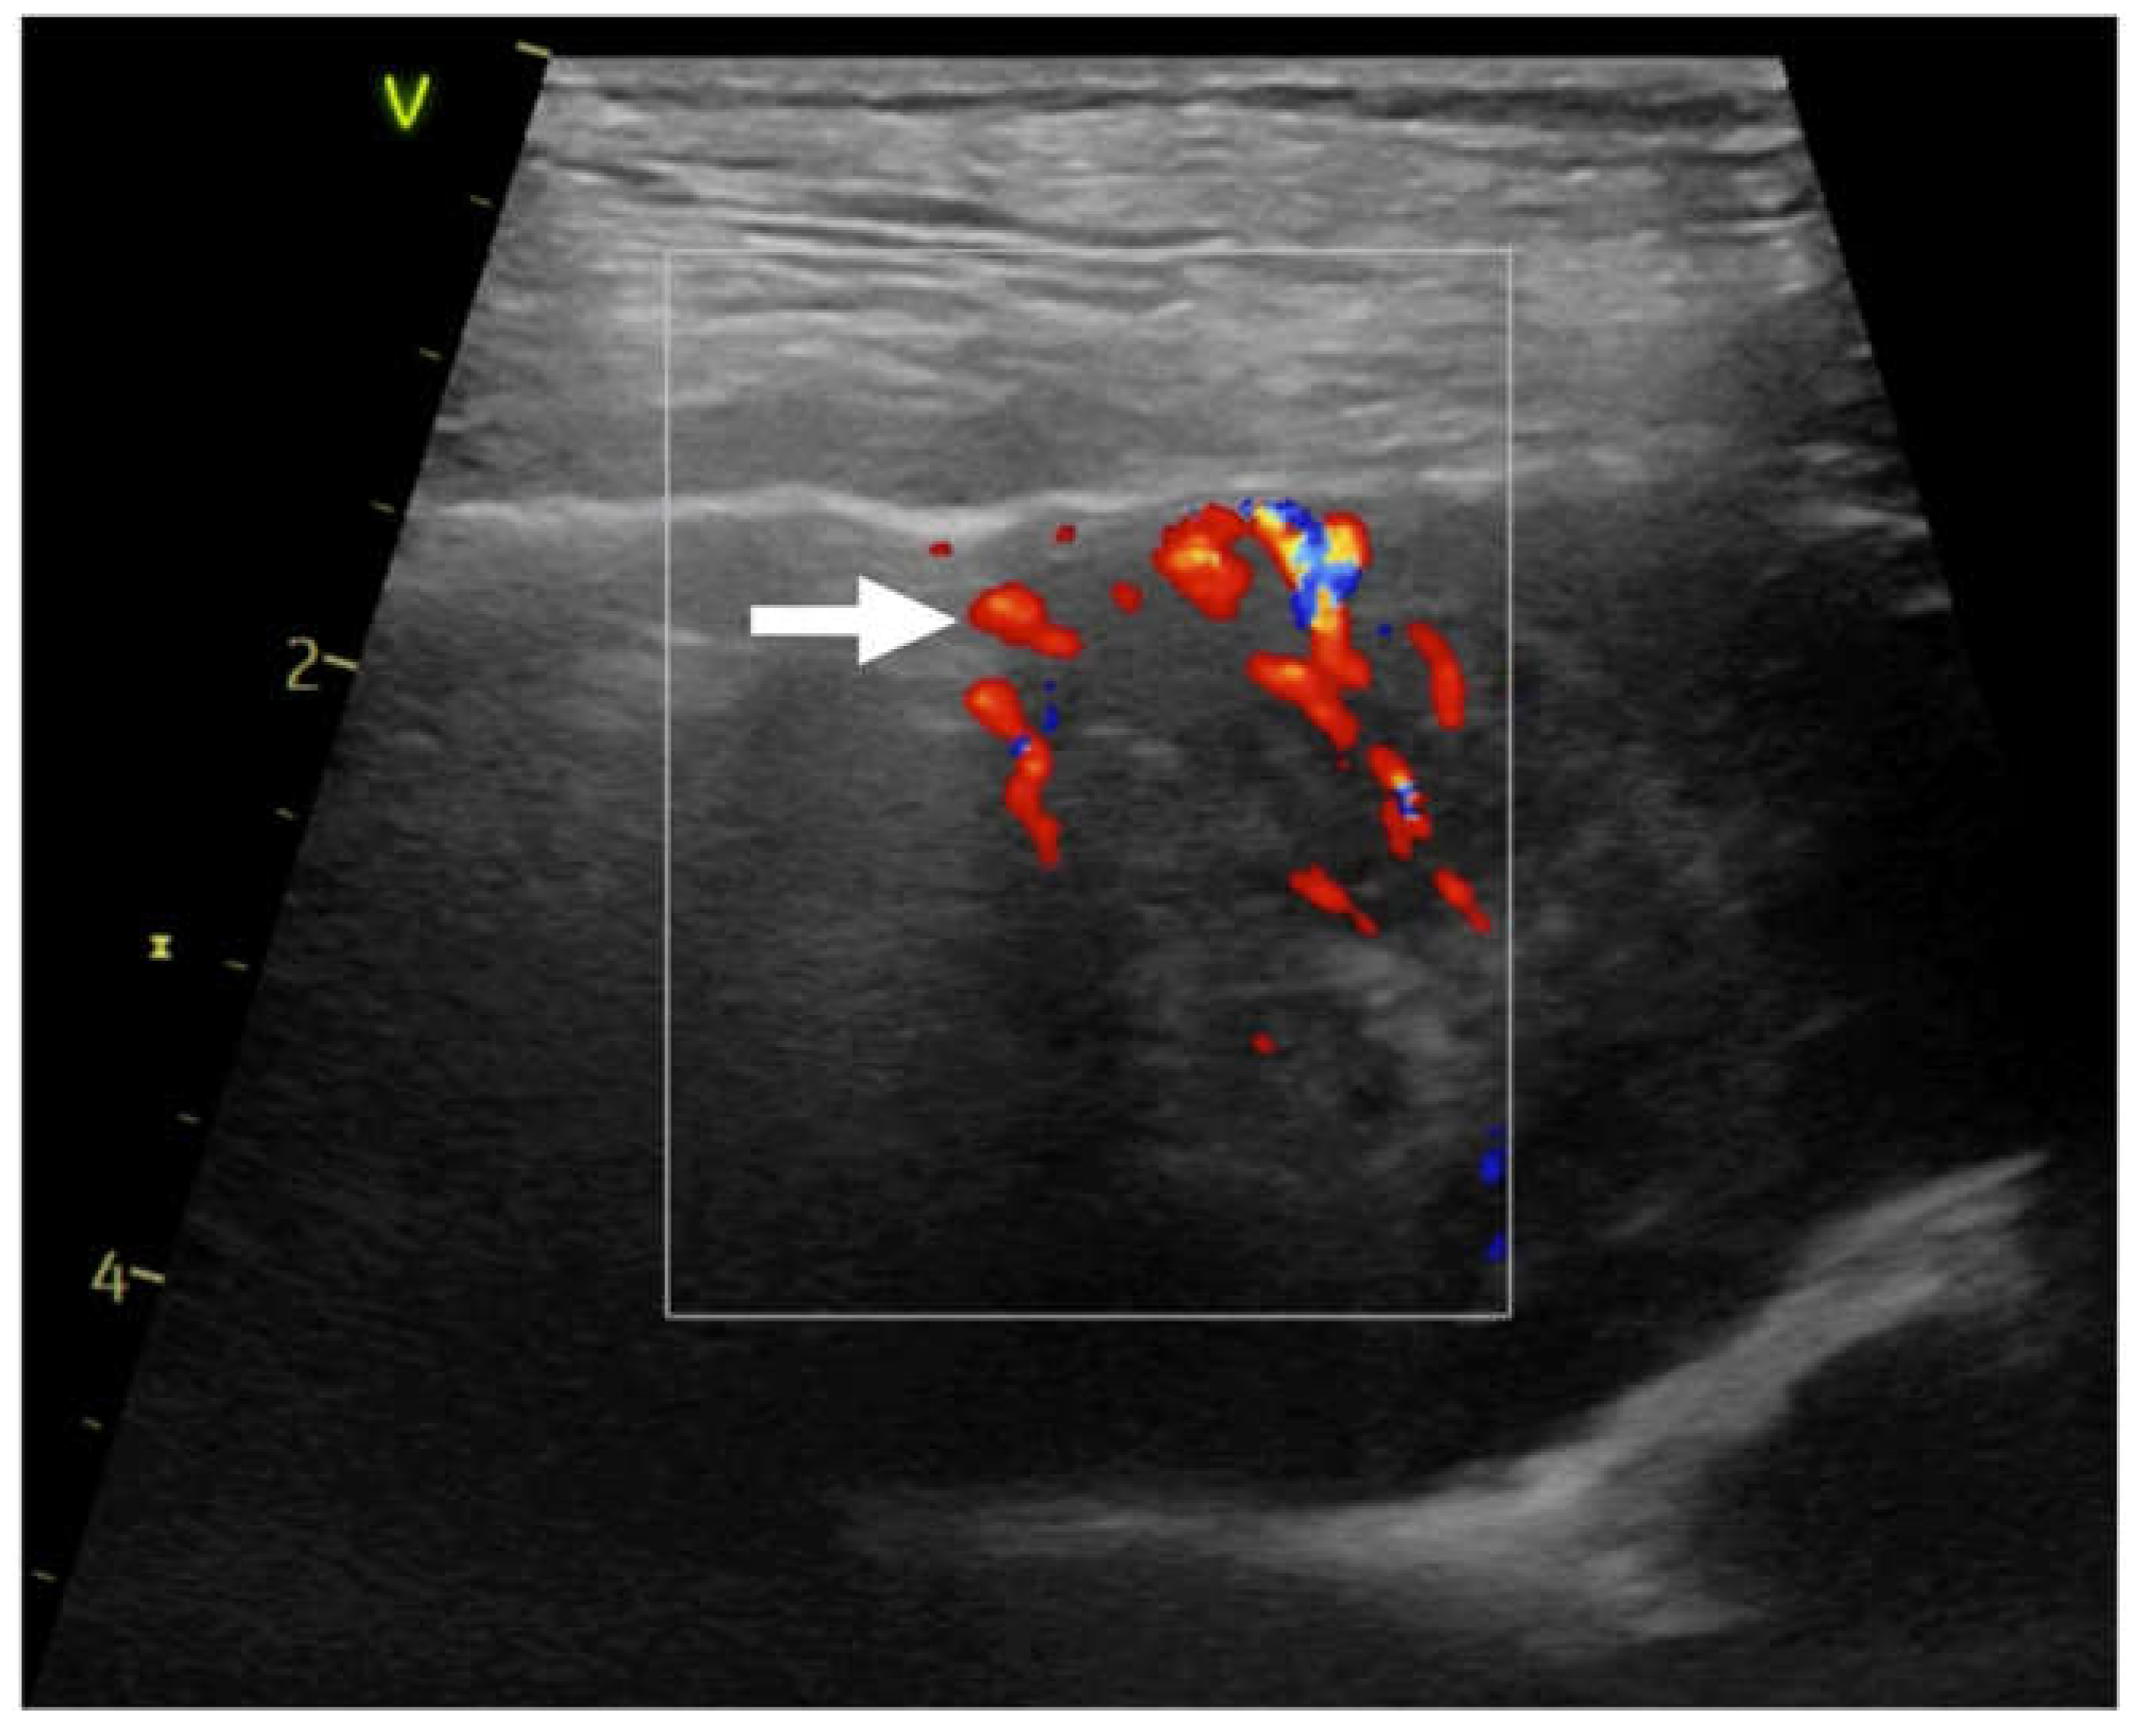

| CD | color doppler | |

| Pv | penetrating type vascularity | |

| Rv | residual type vascularity | |

| Tv | tree-like vascularity | |